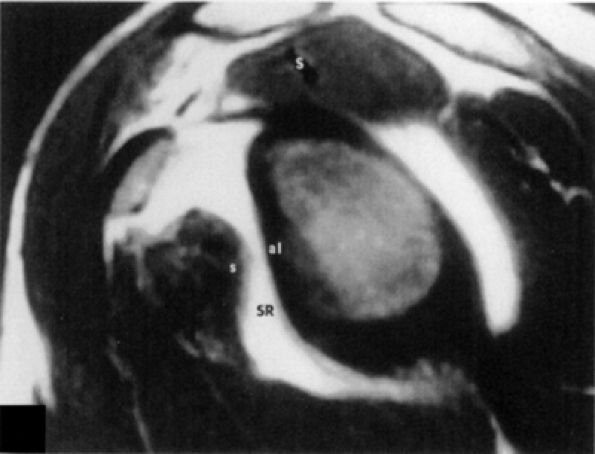

FIGURE 8.90 ● A single type 4 synovial recess. T1-weighted sagittal oblique arthrogram displays absence of the middle glenohumeral ligament, resulting in one large synovial recess above the inferior glenohumeral ligament. S, supraspinatus tendon; SR, synovial recess; s, subscapularis tendon.